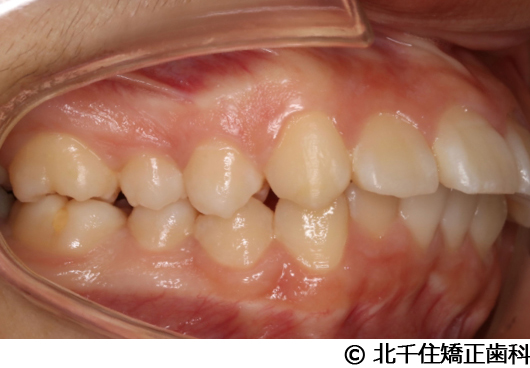

【症例2】上顎前突症

主訴:出っ歯、口元の突出、横顔をきれいにしたい

骨格性の上顎前突、上下顎第一小臼歯4本及び上顎第二大臼歯を抜歯して矯正用アンカースクリューを併用してワイヤー矯正治療(セラミックブラケット)。

骨格性上顎前突に対し、抜歯および矯正用アンカースクリューを併用した矯正治療により歯列および咬合関係の調整を行った症例である。治療後は保定装置を使用し、歯列および咬合の安定維持を目的として定期的な経過観察を行っている。